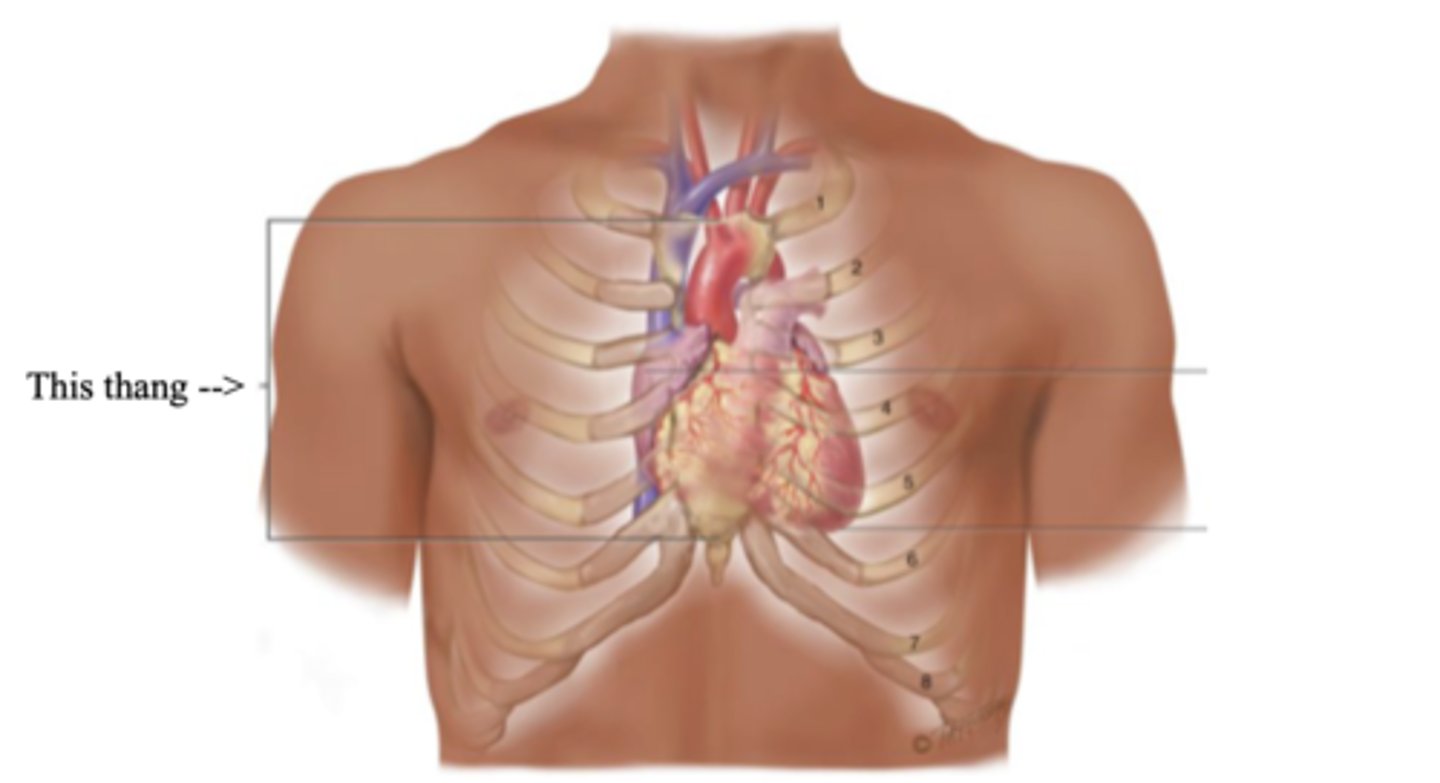

Precordium

The area on the anterior chest overlying the heart and great vessels

Mediastinum

The space located between the lungs where the heart is found

Apex (Heart)

The bottom part of the heart which points down to the left

Base (Heart)

The top broader part of the heart

Right Cardiac Border

An area formed by the right atrium

Left Cardiac Border

An area formed by the left ventricle

Anatomy of the Heart